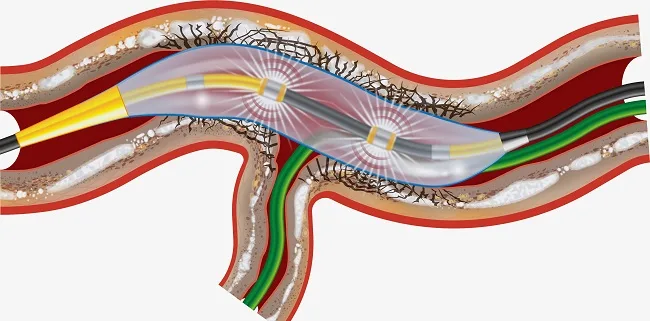

- IVL ( لیتوتریپسی داخل عروقی)

- نکات مهم:

- نتیجه گیری: